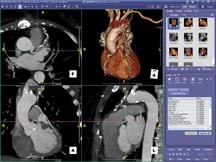

While Carestream’s PACS is also Waddo compliant, the company has developed an underlying streaming technology that “intelligently provides the content as quickly as possible, without requiring the user to wait for the entire data set,” said Maune. For example, if the user is interested in slice 650 in a 2,000-slice CT study, the slices surrounding slice 650 are streamed to the desktop first, enabling the user to begin viewing the study as quickly as possible.

Additional clinical efficiencies, such as the availability of 3D over the Web, will continue to take hold, particularly as workstations become more integrated, notes Maune. “We expect to see greater utilization of hosted storage solutions, an ideal solution for smaller sites such as doctor offices,” he said. Hosted solutions not only reduce IT management expense at the healthcare facility, but also provide disaster recovery and business continuance solutions.